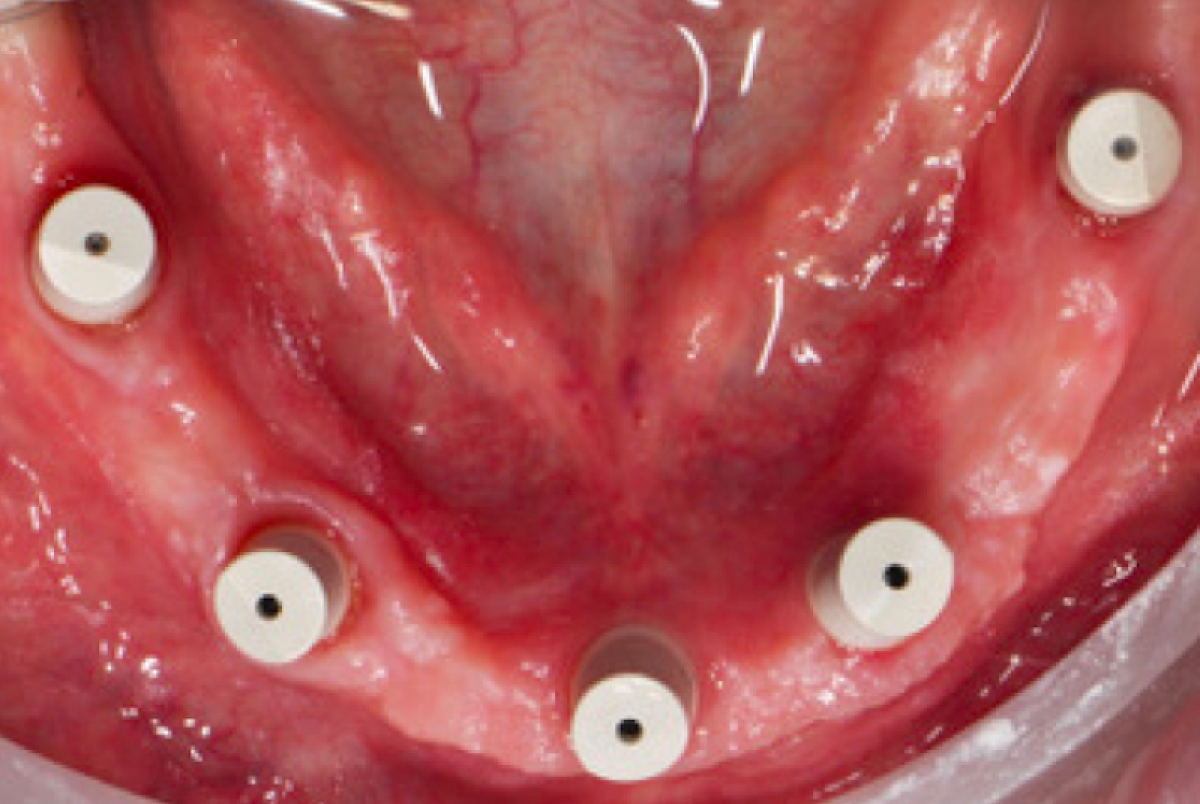

Thereafter, the provisionals were removed from the standard implants and scanbodies (Elos Medtech AB, Lidköping, Sweden) were screwed to the implants (Figure 2).

In this phase it is not possible to collect information about the occlusal relations between the two arches since there is no occlusal stop or stop. Finally, to collect the negative information about the soft tissues adjacent to the prostheses (implant emergence profile and gingival anatomy underlying the pontic elements), the upper and lower provisional were scanned outside the mouth and the third set of impressions ( STL3) was thus obtained. The three series of impressions STL1, STL2, STL3 were then imported into Geomagic Studio 12 software (3D Systems, Rock Hill, SC, USA) and combined using a specific automatic coupling algorithm. Since the gingival tissues scanned in the STL1 and STL3 series were the same, the software identified a good automatic coupling. Thereafter, the STL2 impressions were also coupled thanks to the correspondence between the form of the provisionals acquired in STL2 and STL3.Through the CAD union of the different fingerprints, a single file was obtained, called STL4, which contained the following information: three-dimensional scanbody position, soft tissue architecture, occlusal parameters and esthetic characteristics. The STL4 file was then imported into dental software (Dental Wings, Montréal, QC, Canada) to automatically and certify the position of the implants starting from the scanbodies (Figure 3).